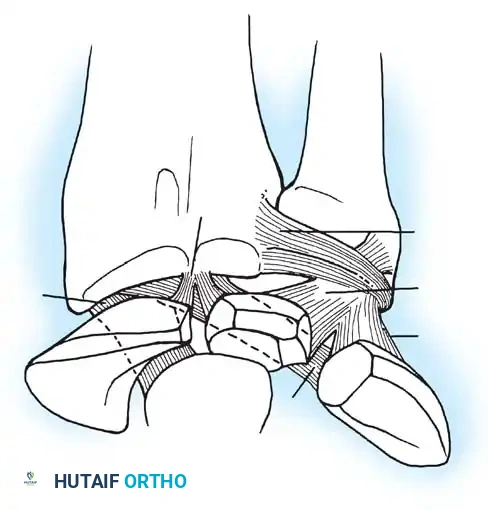

A profound understanding of the dorsal extensor compartments and the underlying capsuloligamentous structures is non-negotiable for safe portal placement. The radiocarpal joint is a complex, multi-axial articulation. The distal radius possesses a normal volar tilt of 11 to 12 degrees and a radial inclination of 22 degrees. This osseous geometry dictates the trajectory of instrument insertion; all radiocarpal portals must be established with a corresponding 10 to 15-degree volar and proximal angulation to avoid iatrogenic scuffing of the articular cartilage.

The intrinsic and extrinsic ligaments of the wrist form a complex stabilizing network. The volar extrinsic ligaments (e.g., radioscaphocapitate, radiolunotriquetral) are stout and provide primary stability, while the dorsal ligaments are thinner. Arthroscopic evaluation allows direct probing of the SL and LT interosseous ligaments to assess for dynamic widening (the "drive-through" sign).

Wrist arthroscopy portals are anatomically defined by their relationship to the six dorsal extensor compartments. Precise portal placement is critical to avoid injury to cutaneous nerves, extensor tendons, and articular cartilage.

Radiocarpal Portals

- 1-2 Portal: Located between the first compartment (APL, EPB) and the second compartment (ECRL, ECRB). It is situated in the anatomic snuffbox. Risk: The superficial branch of the radial nerve (SBRN) and the radial artery.

- 3-4 Portal: The primary viewing portal. Located between the third compartment (EPL) and the fourth compartment (EDC), just distal to Lister's tubercle. It provides an excellent panoramic view of the SL ligament, volar ligaments, and the radial aspect of the TFCC.

- 4-5 Portal: The primary working portal. Located between the fourth compartment (EDC) and the fifth compartment (EDM). It provides direct access to the TFCC and the LT ligament.

- 6R Portal: Located immediately radial to the sixth compartment (ECU tendon). Used for viewing the ulnar periphery of the TFCC and the ulnocarpal ligaments.

- 6U Portal: Located immediately ulnar to the ECU tendon. Risk: The dorsal sensory branch of the ulnar nerve (DSBUN).

Midcarpal Portals

The midcarpal joint is a separate synovial cavity and must be evaluated independently to assess the distal aspects of the SL and LT ligaments and the capitohamate articulation.

* Midcarpal Radial (MCR) Portal: Located approximately 1 cm distal to the 3-4 portal, in a palpable soft depression between the capitate, scaphoid, and lunate. It is in line with the radial border of the third metacarpal.

* Midcarpal Ulnar (MCU) Portal: Located approximately 1 cm distal to the 4-5 portal, aligned with the axis of the fourth metacarpal, providing access to the triquetrohamate and lunotriquetral articulations.

Volar Portals

While less commonly used, volar portals (volar radial and volar ulnar) are gaining traction for specific indications, such as evaluating dorsal capsular avulsions or repairing volar TFCC tears. These require meticulous blunt dissection due to the proximity of major neurovascular bundles (radial artery, median nerve, ulnar artery/nerve).